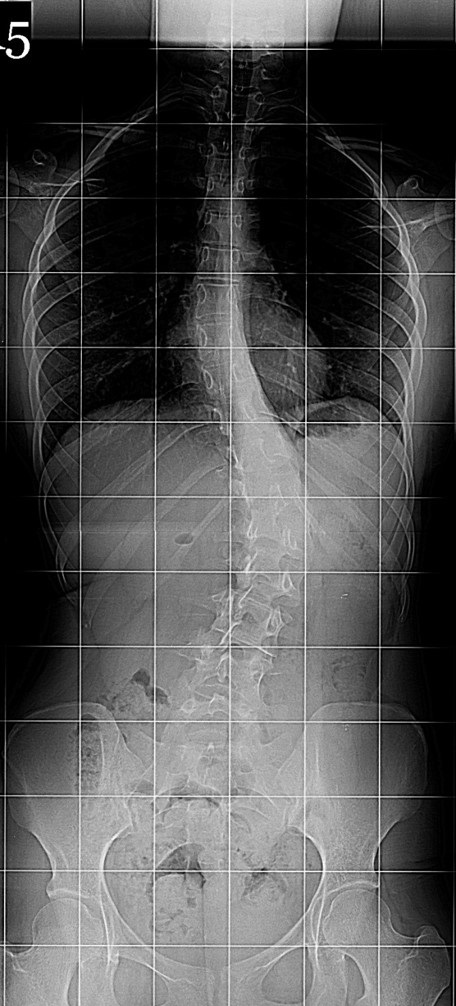

20 Yaşında Kadın Hasta

Boy: 171.3cm.

Kilo: 66kg

Rib hump lomber 10 derece

Ameliyat Öncesi